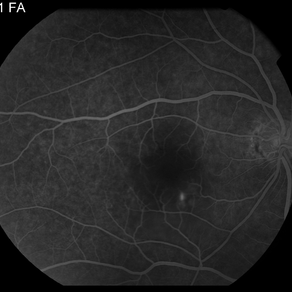

AMPPE

Apr 29 2014 by David W. Faber, MD

24-year-old female presented with central blurry vision for 3-5 days. Vision : OD 20/20, OS 20/100

Photographer: Jodi Schiele, Rocky Mountain Retina Consultants, Salt Lake City, Utah

Condition/keywords: acute multifocal placoid pigment epitheliopathy (AMPPE)